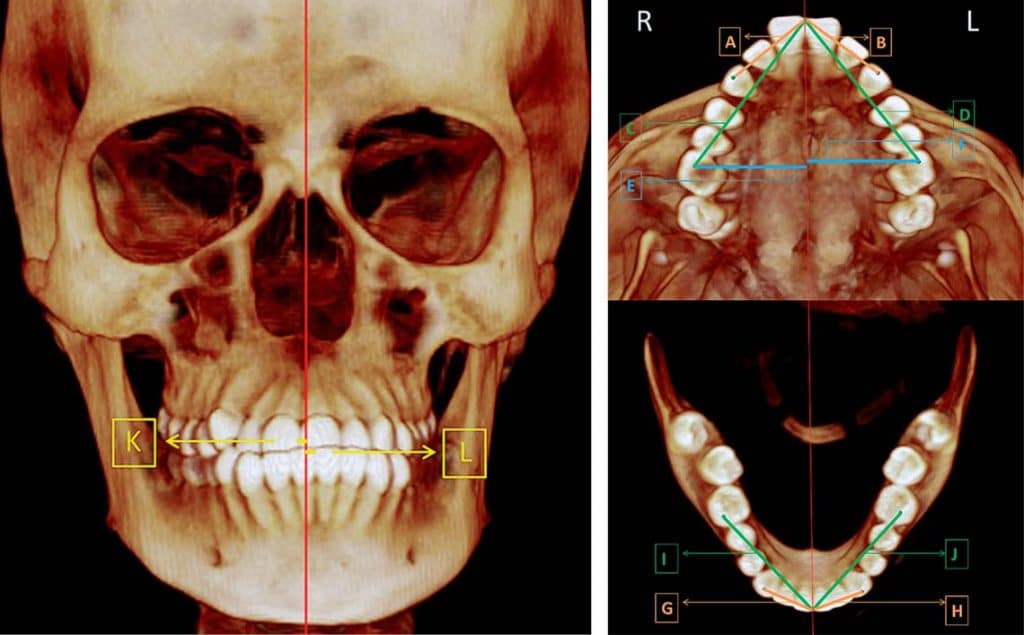

A través de la radiología, se conocen diferentes sistemas auxiliares de diagnóstico especializados de exploración, que nos proporcionan una información que ningún otro método nos puede ofrecer, tomando en consideración los avances técnico y científicos. En la materia de radiología, la actualización y aplicación de estos nuevos métodos, son necesarios para poder obtener el conocimiento básico y avanzado en el manejo de la interpretación radiográfica, así mismo, en conjunto con otros estudios clínicos, poder tener un diagnóstico acertado en las radiografías.

La radiografía panorámica permite la observación de ambos maxilares y la dentición, presentando una serie de relaciones únicas entre estas estructuras que no pueden ser encontradas en otro tipo de radiografías.